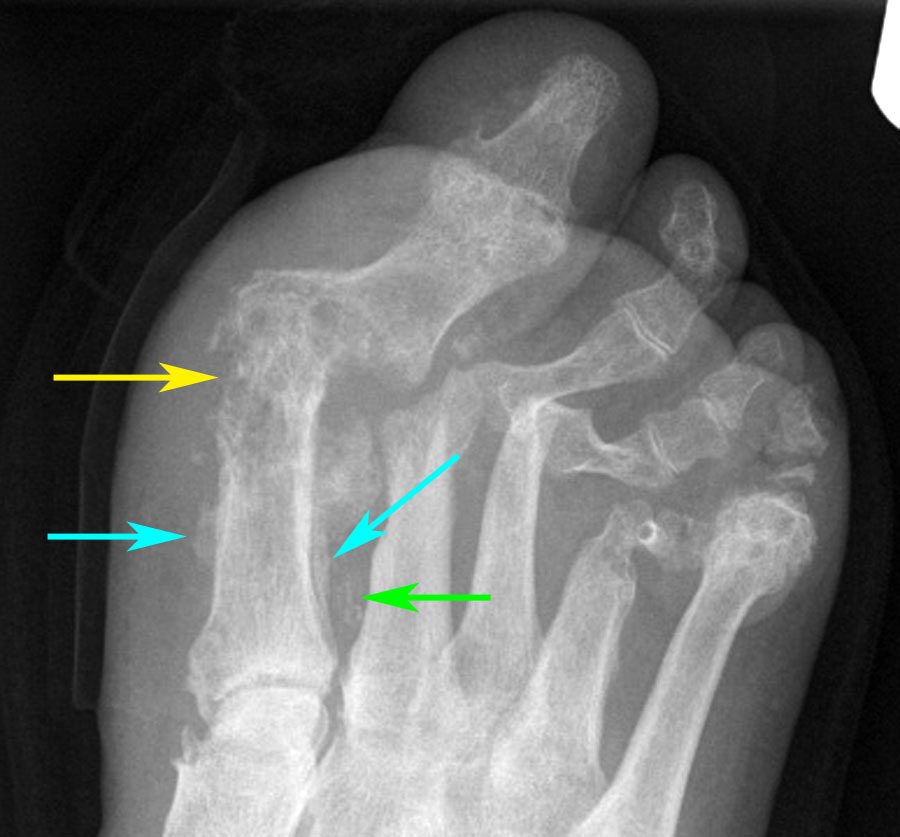

There is extensive bony destruction of the first metatarsal with overlying soft tissue swelling. This destruction is well shown on a magnified view (yellow arrow). Note also periosteal reaction (blue arrows) and vascular calcification (green arrow). = Charcot foot